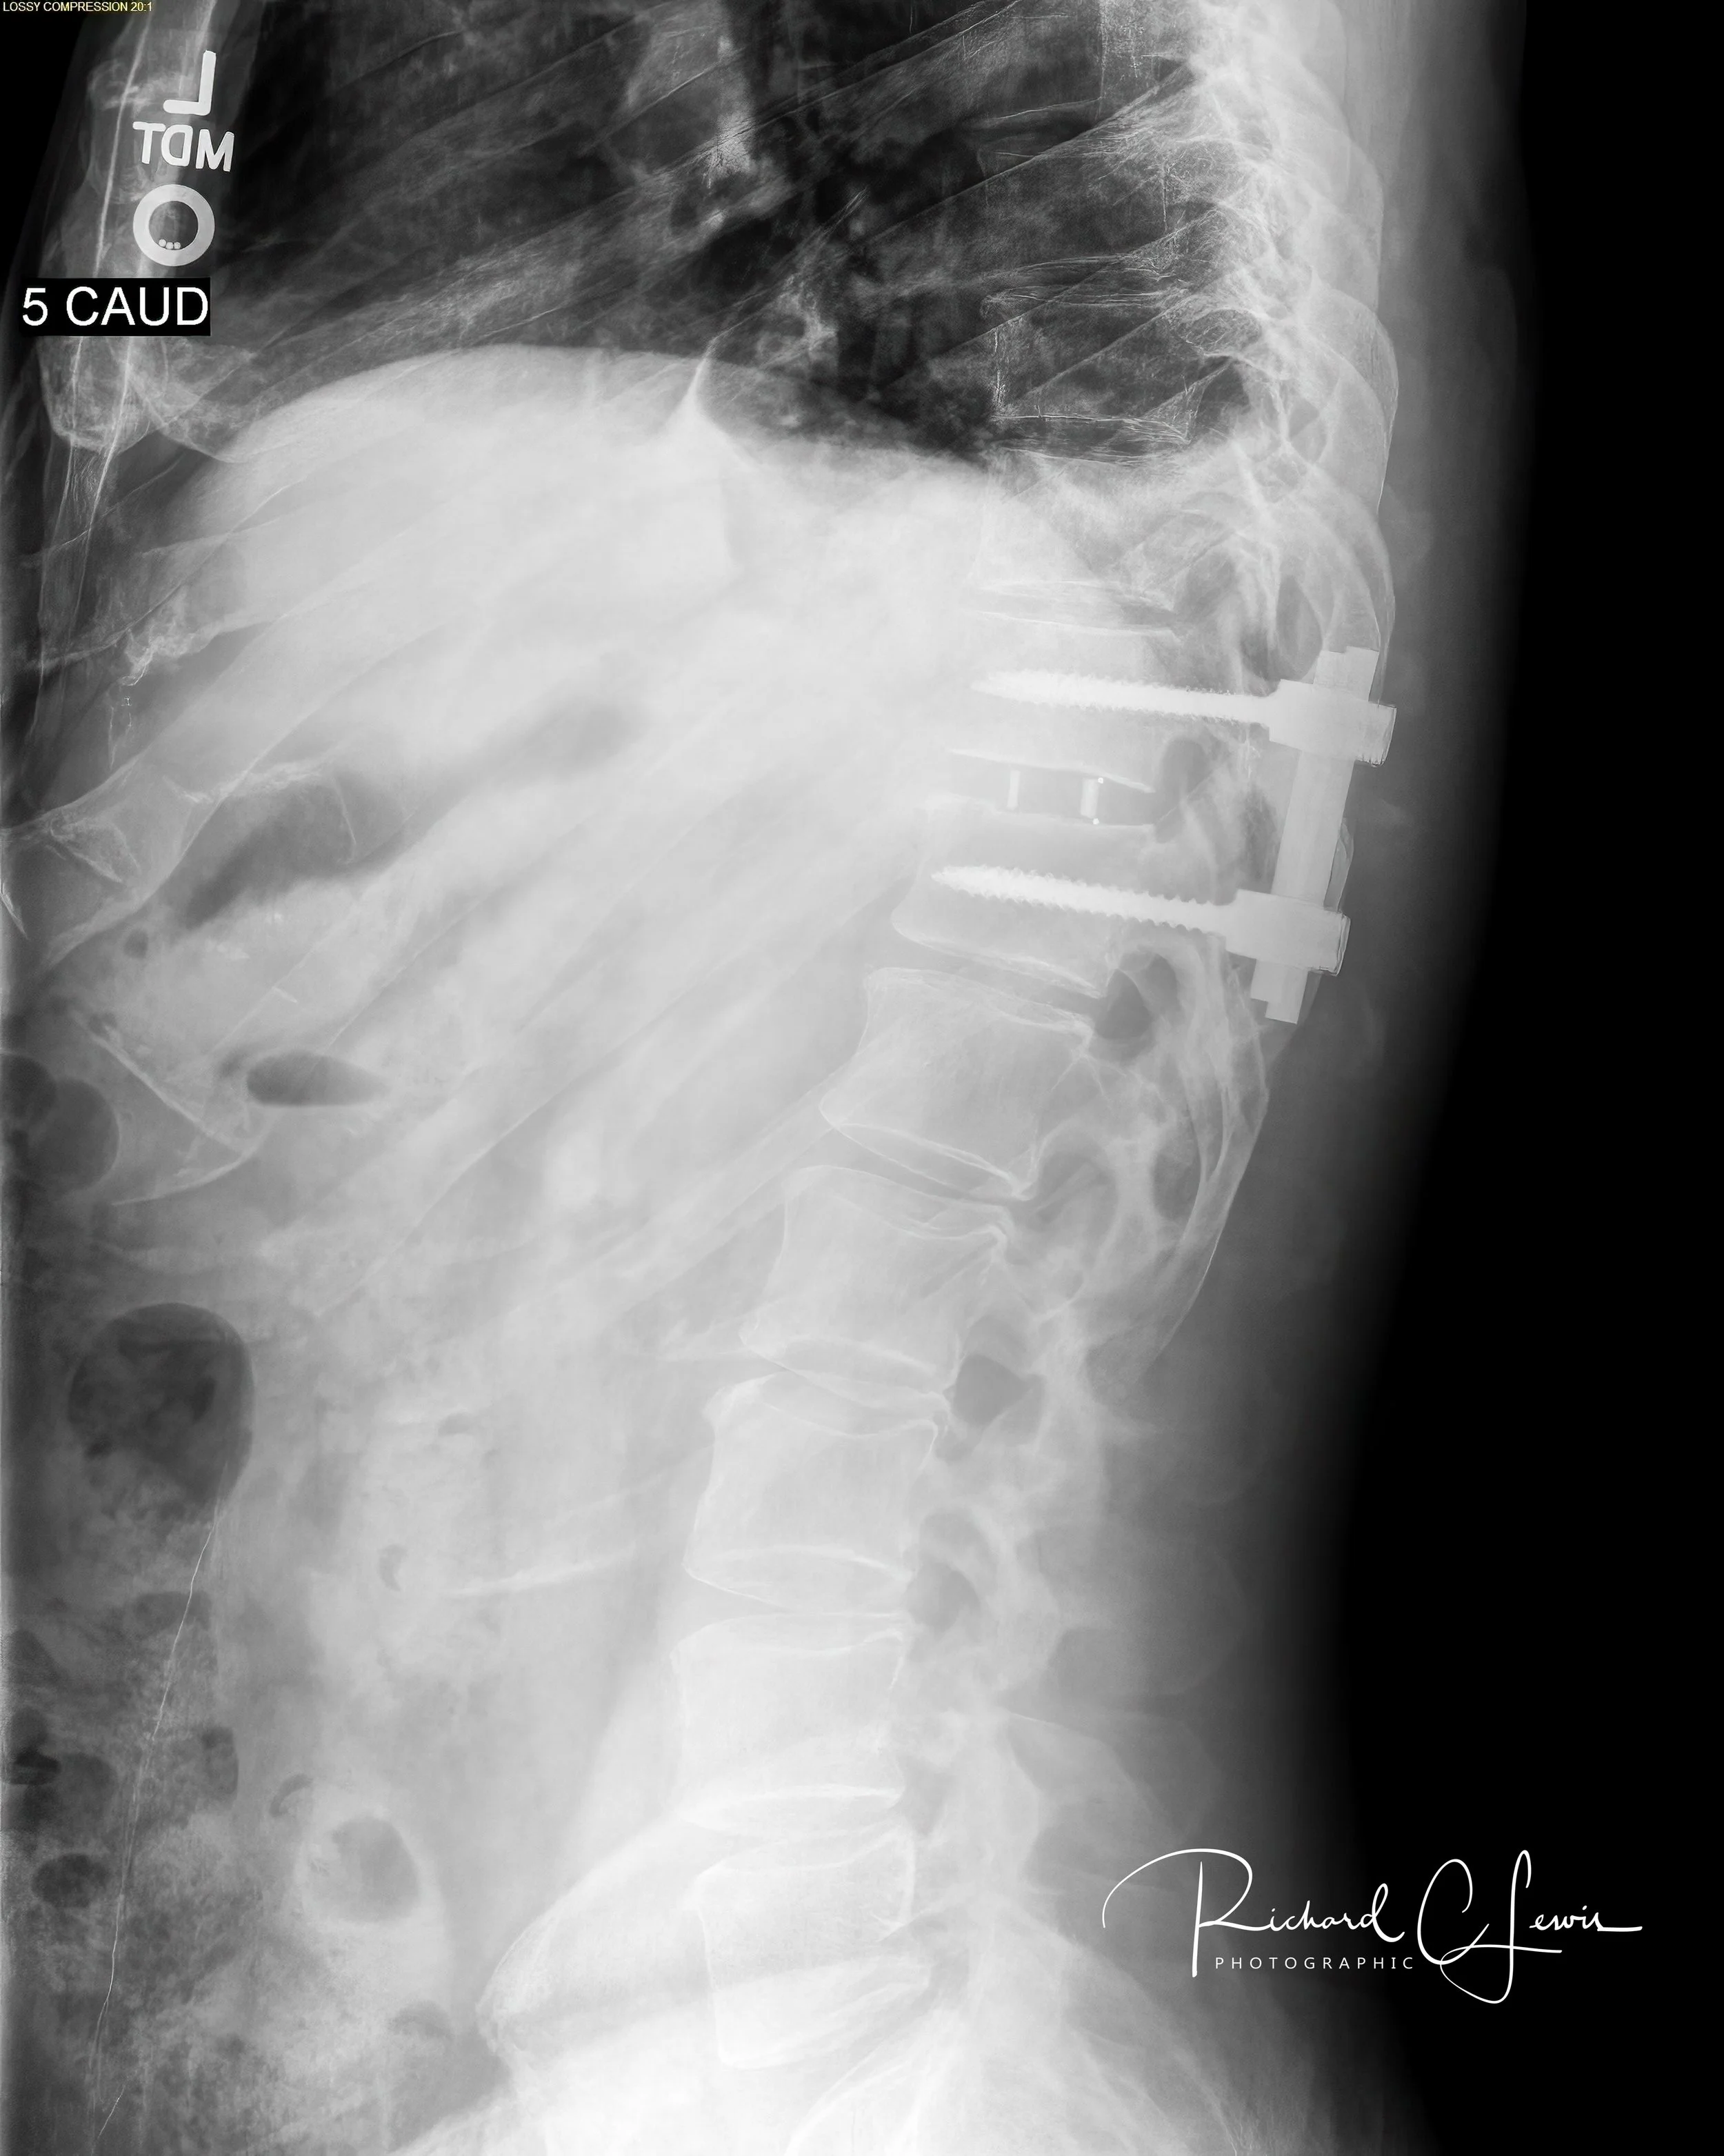

To stabilize the ruins, I underwent a spinal fusion and disk replacement. Brutal. That is the only word for it. The surgeons were architects of steel and bone, but while they rebuilt the structure, the house was still burning. I was plunged into the dark years of chronic pain. My nerves remained trapped in a state of hyper-excitability, and the soft tissues were suffocated by dense, non-compliant scar tissue.